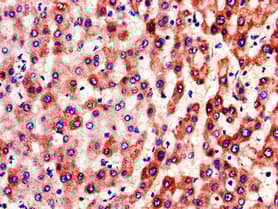

Anti-Factor IX/PTC antibody(ab236279)

Rabbit Polyclonal Factor IX/PTC antibody. Suitable for IHC-P, ICC/IF and reacts with Human samples. Immunogen corresponding to Recombinant Fragment Protein within Human Coagulation factor IX aa 100-250.

Applications ICC/IF, IHC-P

Species Reactivity Human